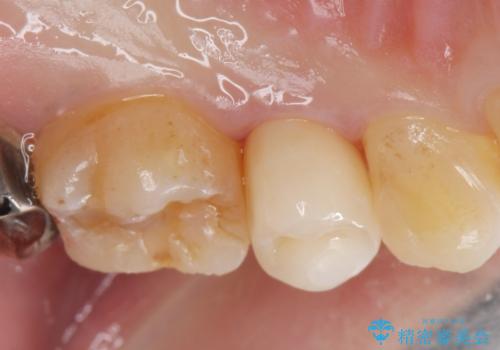

白くて適合の良い被せ物が入りました。

セラミックは劣化することがなく虫歯の再発のリスクが低くなります。